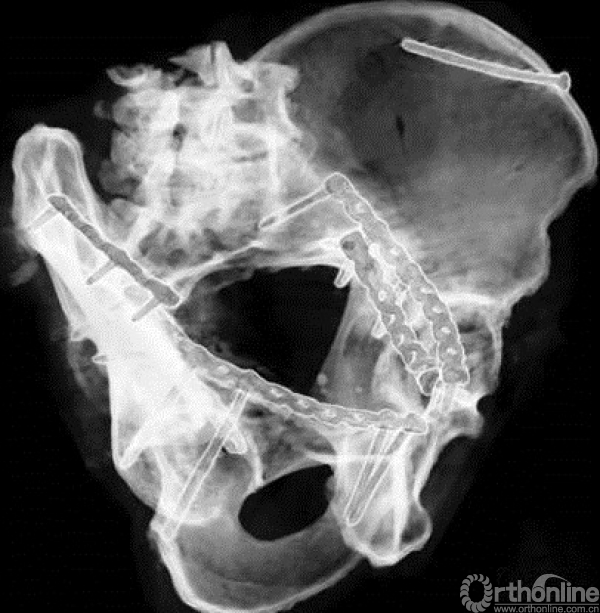

三块钢板

1.上侧钢板与四个关键螺钉

需要沿骨盆缘放置来进行下方骨块的提拉

钢板可用顶棒进行提拉复位,最后可用术中塑形器进行最终塑形。

四个关键螺钉(上一章已经讲过)

1.骶髂关节前处的螺钉;

2.后柱的螺钉;

3.髋臼柱螺钉;

4.耻骨支螺钉。

2.第二块钢板

内侧钢板,该钢板需要过预弯。通过钢板的挤压来复位内移的方形区,沿骨盆缘的内侧进行置放。

当方形区有较大独立骨块的时候,也可以采用T形钢板。

需要注意螺钉不要进入关节

3.第三块钢板、髂坐钢板

来进行后柱的骨折复位,同时可以防止方形区的移位。这三块钢板可单独使用,也可同时使用,根据骨折类型决定。